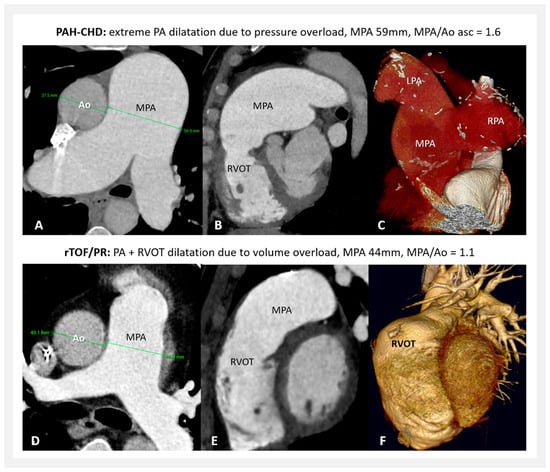

- Sixty patients with pulmonary arterial hypertension associated with congenital heart defect (PAH-CHD) (47 patients with unoperated shunt defects; 10 after surgical or interventional shunt closure, or with small defects; and 3 with congenital portopulmonary PH); all with the long-term (median 15 years) confirmed hemodynamics of severe pulmonary artery pressure overload (with mean pulmonary artery pressure 60 mmHg (median), and pulmonary vascular resistance 9.3 Wood units (median)).

- Sixty-four patients with a repaired Tetralogy of Fallot with isolated “free” pulmonary regurgitation (rTOF/PR) had the hemodynamics of pure proximal pulmonary artery volume overload. The median age at complete TOF repair was 5 years, and the median follow-up after repair was 22 years. The PA data analysis was performed at the time period before any reintervention due to pulmonary regurgitation was performed. In this study, patients with Tetralogy of Fallot with absent pulmonary valve syndrome, patients with pulmonary conduit or any other valve implantation during primary complete repair, or patients with any presence of significant (valvar, subvalvar, or supravalvar) pulmonary stenosis or significant pulmonary artery branch deformation during follow-up were not included.